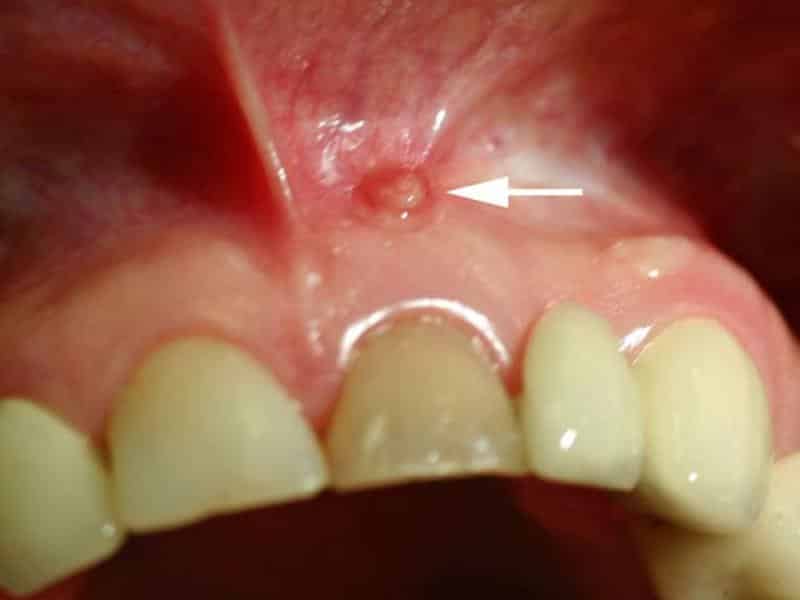

1. Визуальный осмотр: Первоначально стоматолог проводит осмотр полости рта. Врач обращает внимание на наличие опухолей, изменений в деснах и других признаков, которые могут указывать на наличие кисты. Однако визуальный осмотр не всегда может дать полную картину, поэтому необходимы дополнительные методы диагностики.